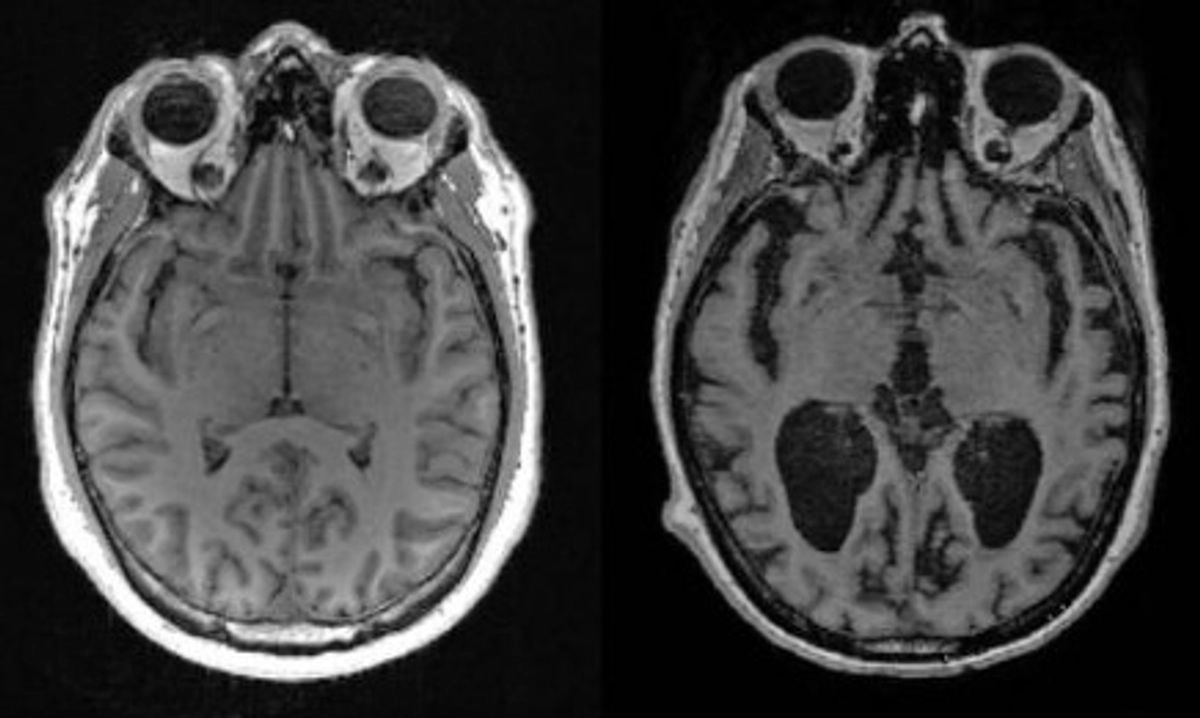

En el estudio, los científicos utilizaron un tipo avanzado de método de análisis químico por espectroscopia de masas para medir los niveles de trazas de unos 30 metales diferentes en muestras de cerebro y sangre de una serie de personas, incluidas las cognitivamente sanas, las que se encontraban en una fase inicial de demencia y las que padecían Alzheimer avanzado.

El análisis reveló que el litio era el único metal con niveles marcadamente diferentes entre los grupos, que además parecían cambiar en las fases más tempranas de la pérdida de memoria.